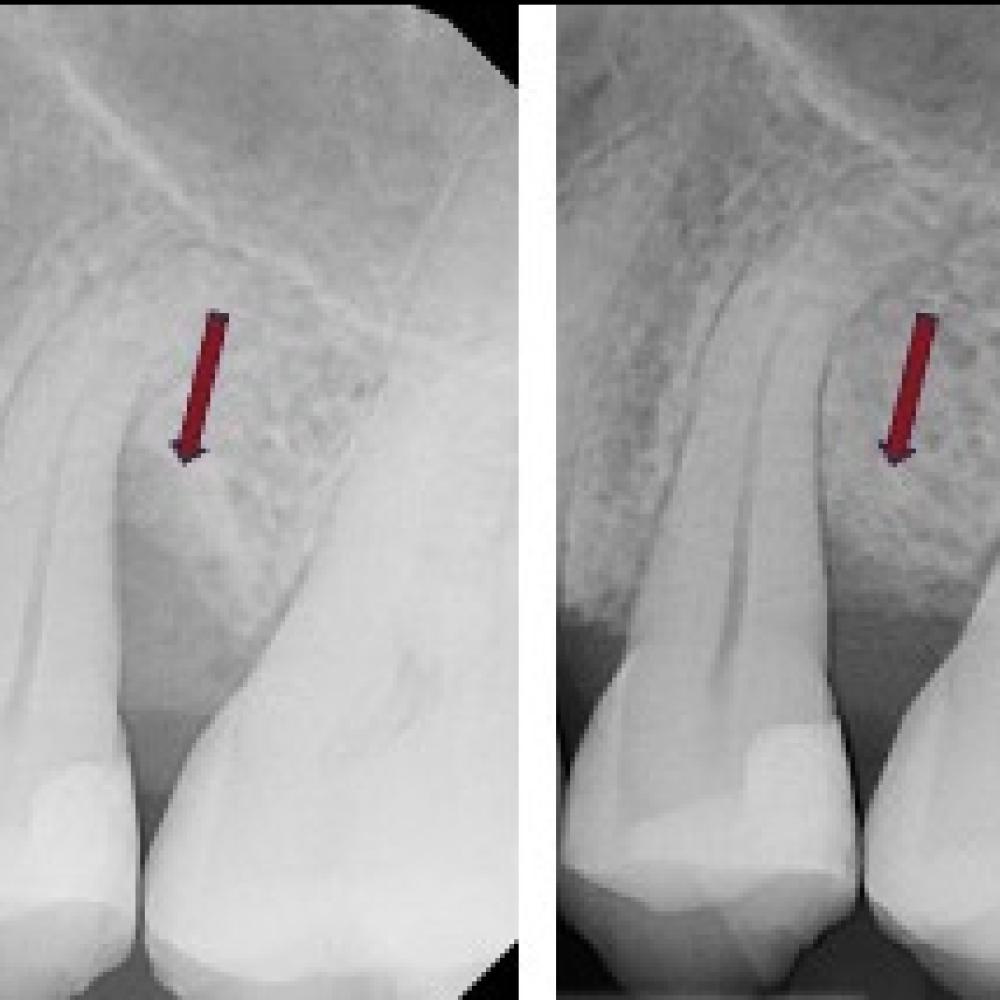

What can be done to prevent tooth loss or increase bone formation for implant placement? Guided Tissue Regeneration (GTR) is a procedure that enables bone and tissue to grow around an endangered tooth.

In GTR therapy for teeth, the soft (gum) tissue is surgically separated from the endangered tooth and the tooth surface is thoroughly cleaned. Infected tissues are removed from the area. Next a biocompatible material is placed into the defect surrounding the tooth and the soft tissue is sutured back into place.